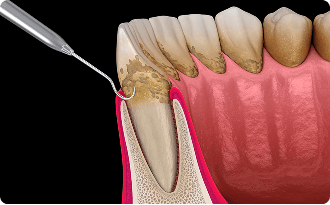

歯石

歯石はプラーク(バイオフィルム)が石灰化したもので、頑固にこびりつくため、ブラッシングだけで落とすことはできず、歯科医院で使用する専用の器具を使用して取り除くしかありません。また歯石は歯茎の上だけでなく、歯と歯茎の隙間して歯根の部分で歯石を作るため、歯茎の上の歯石を取り除いても歯根に付着している歯石を取り除かないと歯周病は改善しません。歯周病が改善しない人の多くは歯根に歯石が付着してることが多いです。

縁下歯石とり(SRP:歯石とり、根面の滑沢化)

ここからが本格的な歯周病治療になります。歯茎の中にある隠れ歯石を除去していきます。隠れ歯石のことを歯茎の縁よりも下の隠れている歯石ということで縁下歯石と呼びます。歯周ポケットが4mm以上ある場合は、縁下歯石が付着している場合が多いです。歯茎の中を触って行くため、処置中チクチクと感じたりします。そのため、麻酔をかけながらすることが多いです。右上、右下、左上、左下と4回程度に分けることが多いです。